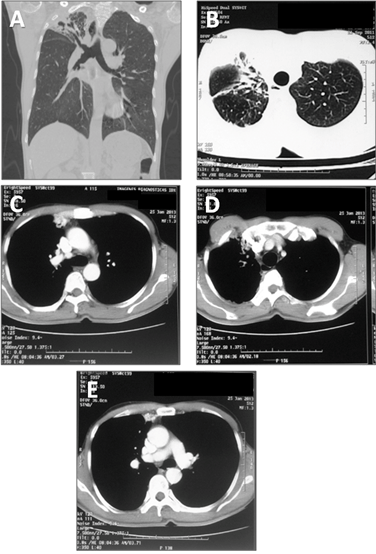

Figure 2: Pulmonary angiography using OmnipaqueTM contrast media. (A) Selective angiography of the right pulmonary artery showing no intrapulmonary fistula (B) Selective angiography of the right subclavian artery that illustrates a normal subclavian artery (arrow 1), hypertrophic right mammary artery with multiple collaterals to the right upper lobe (arrow 2). It shows rapid filling of right superior pulmonary vein proving the diagnosis of systemic-pulmonary arteriovenous fistula (arrow 3) (C) The venous phase of selective arteriography of the right internal mammary artery shows a high flow fistula with large collaterals from the mammary artery to the pulmonary vein. (D) For selective embolization of the internal mammary artery, two coils (Interlock, Boston Scientific) and two vascular closure devices (Amplatzer Vascular Plug, AGA Medical Corp.) were used. Complete occlusion of the mammary artery is evident, although the filling of the pulmonary vein persists through two small branches from of the right subclavian artery.

A 47-year-old male presented to our institution with massive hemoptysis in which approximately 150 cm3 of blood was expectorated at least twice a week in a period of 18 months. He had been treated in another institution for pulmonary tuberculosis six years ago. This was after the diagnosis with serial spontaneously sputum stains positive for acid-fast bacilli. He had to repeat this treatment in spite of the following negative smears because of the persistent hemoptysis, which had also increased in volume and frequency. Despite recurrent hemoptysis, the patient was brought to our institution four years after he finished treatment. On examination, he had low weight, and we found a continuous murmur at the level of the right superior thorax. We did not find vascular lesions in his mouth or on his skin. The rest of the physical examination was normal. The laboratory data including complete blood count and blood chemistries were also normal. Pulse oximetry at rest showed normal values. The patient denied any past history of liver disease. Computed tomography (CT) scan of chest revealed signs of volume loss and bronchiectasis involving the right superior lobe. We found an unusual image of vascular characteristic at the level of the right internal mammary artery. There were no caverns or suspicious images of pulmonary arteriovenous malformations (Figure 1). We decided to undertake an angiographic evaluation in which we observed a high flow systemic to pulmonary arteriovenous fistula from the internal mammary and right subclavian arteries, to the right upper lobar veins. We proceeded to perform embolization using two interlock coils and two amplatzer vascular plugs until the internal mammary artery was completely cut-off (Figure 2). The spirometric data showed a FEV1=2820 mL (82% ref), FVC=3050 mL (69% ref), and %FEV1/FVC=92. The patient was discharged after two days of hospital stay with resolution of the hemoptysis. The patient remains asymptomatic for dyspnea and hemoptysis.